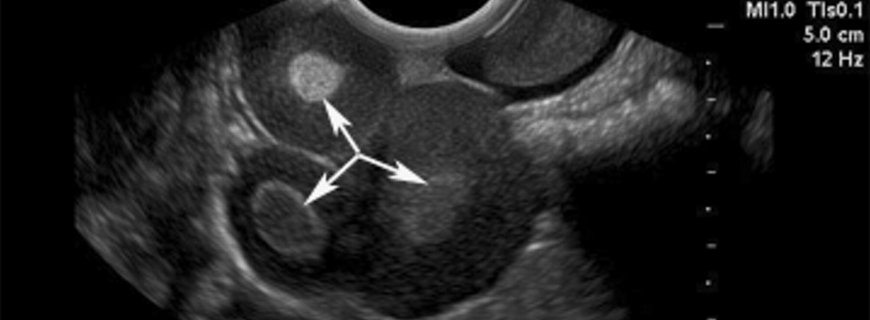

Yumurtalık kistleri yumurtalığın içinde ya da yüzeyindeki sıvı ile dolu keselerdir. Çoğu yumurtalık kisti fizyolojiktir ve genellikle belirtisiz seyreder. En sık görülen fizyolojik kistler folliküler...

Folliküler Kist Nedir ve Neden Oluşur?Folliküler kist yumurtalık dokusunda bulunan fizyolojik bir yumurtalık kistidir. Yumurtalık yüzeyinde bir köpük gibi görünen, berrak ya da saman sarısı renginde s...

Korpus Luteum Kisti Nedir?Normal bir folliküler kist yumurtalık follikülü açığa çıkardığında sonuçta oluşan yapıya korpus luteum kisti denir. Çoğu korpus luteum kisti kendiliğinden kaybolur. Bazen k...

Teka Lutein Kisti Nedir ve Neden Oluşur?Teka lutein kistleri yumurtalıkları ılımlıdan çok büyüğe kadar büyüten fizyolojik yumurtalık kistleridir. Genellikle yumurtalıkların hormonlar tarafından çok uy...

Endometriomalar, rahim iç duvarına benzer tipte bezlerin bulunabildiği iyi huylu, bir yumurtalık kistidir. Bu hastalarda genellikle karın içinin diğer bölgelerinde de endometriozis denen benzer hastal...